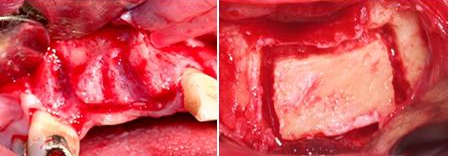

Situação que o paciente se apresentou no consultório para colocação de implantes e restabelecimento da estética e função dos dentes. Como o tecido ósseo havia sido reabsorvido, para a realização dos implantes, enxerto de ósseo e plasma rico em plaquetas (PRP) teve que ser realizado. Na fotografia vemos os parafusos, fixando os blocos de osso que colocados, e recobertos com PRP (Fotos).

Nestas fotografias estão: O PRP utilizado junto com o enxerto de osso e os implantes colocados 6 meses após a cirurgia.